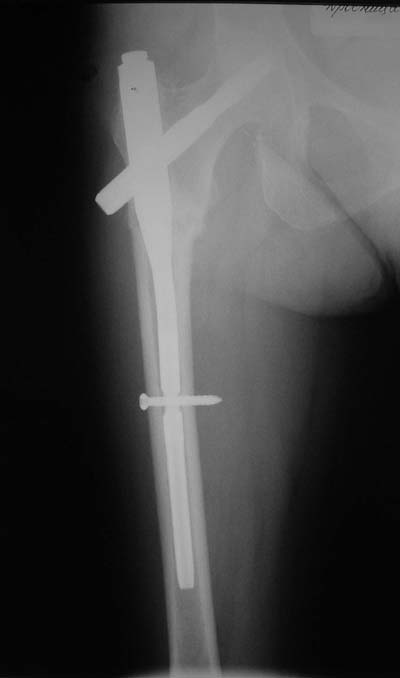

Не думаю так. см вложение.

> Не думаю так. см вложение.

Для такого перелома вполне может быть использован диафизарный штифт, который отечественного производства я даже боюсь считать во сколько раз дешевле... Недавно несколько примеров я закидывал.